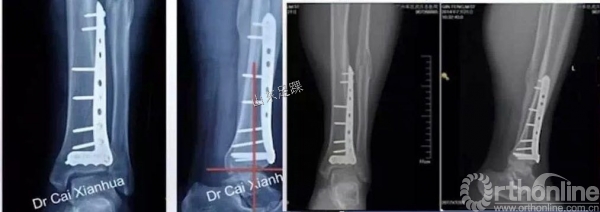

钢板位置

关节面复位

复位胫骨远端关节面时,需要辨认3个主要的骨折块:Volkmann骨块、Chaput骨块和内踝骨块。

关节面复位要由后向前、由外向内的顺序进行,后方的Volkmann骨块是复位的关键。

胫骨骨折主要接骨板放置在压力侧;骨缺损明显,增加辅助钢板。